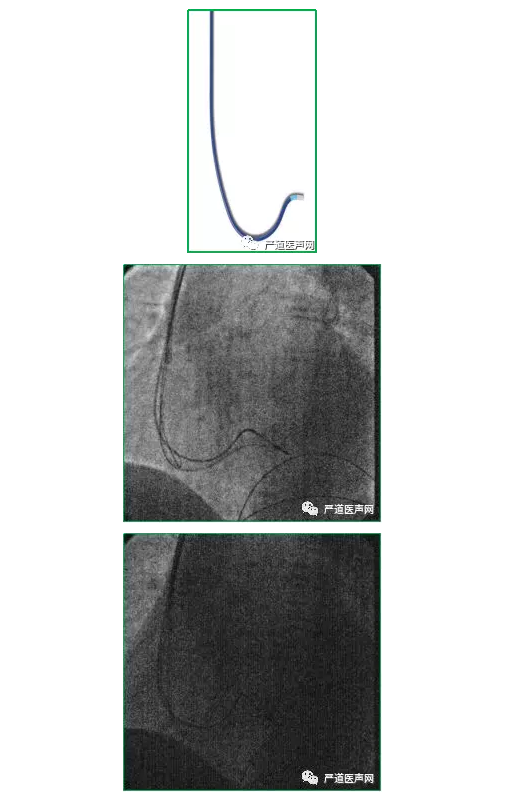

冠状窦口存在瓣膜(Thebesian瓣)

55/75 hearts:73%

CS开口处的Thebesian 瓣

冠状窦口存在瓣膜术中可能的征象:

● 1.导线、EP电极及PTCA钢丝等入CS,但指引导管不能进入;

● 2.通过指引导管在房内造影,可见窦口常成平面,似“刀削状”影像。